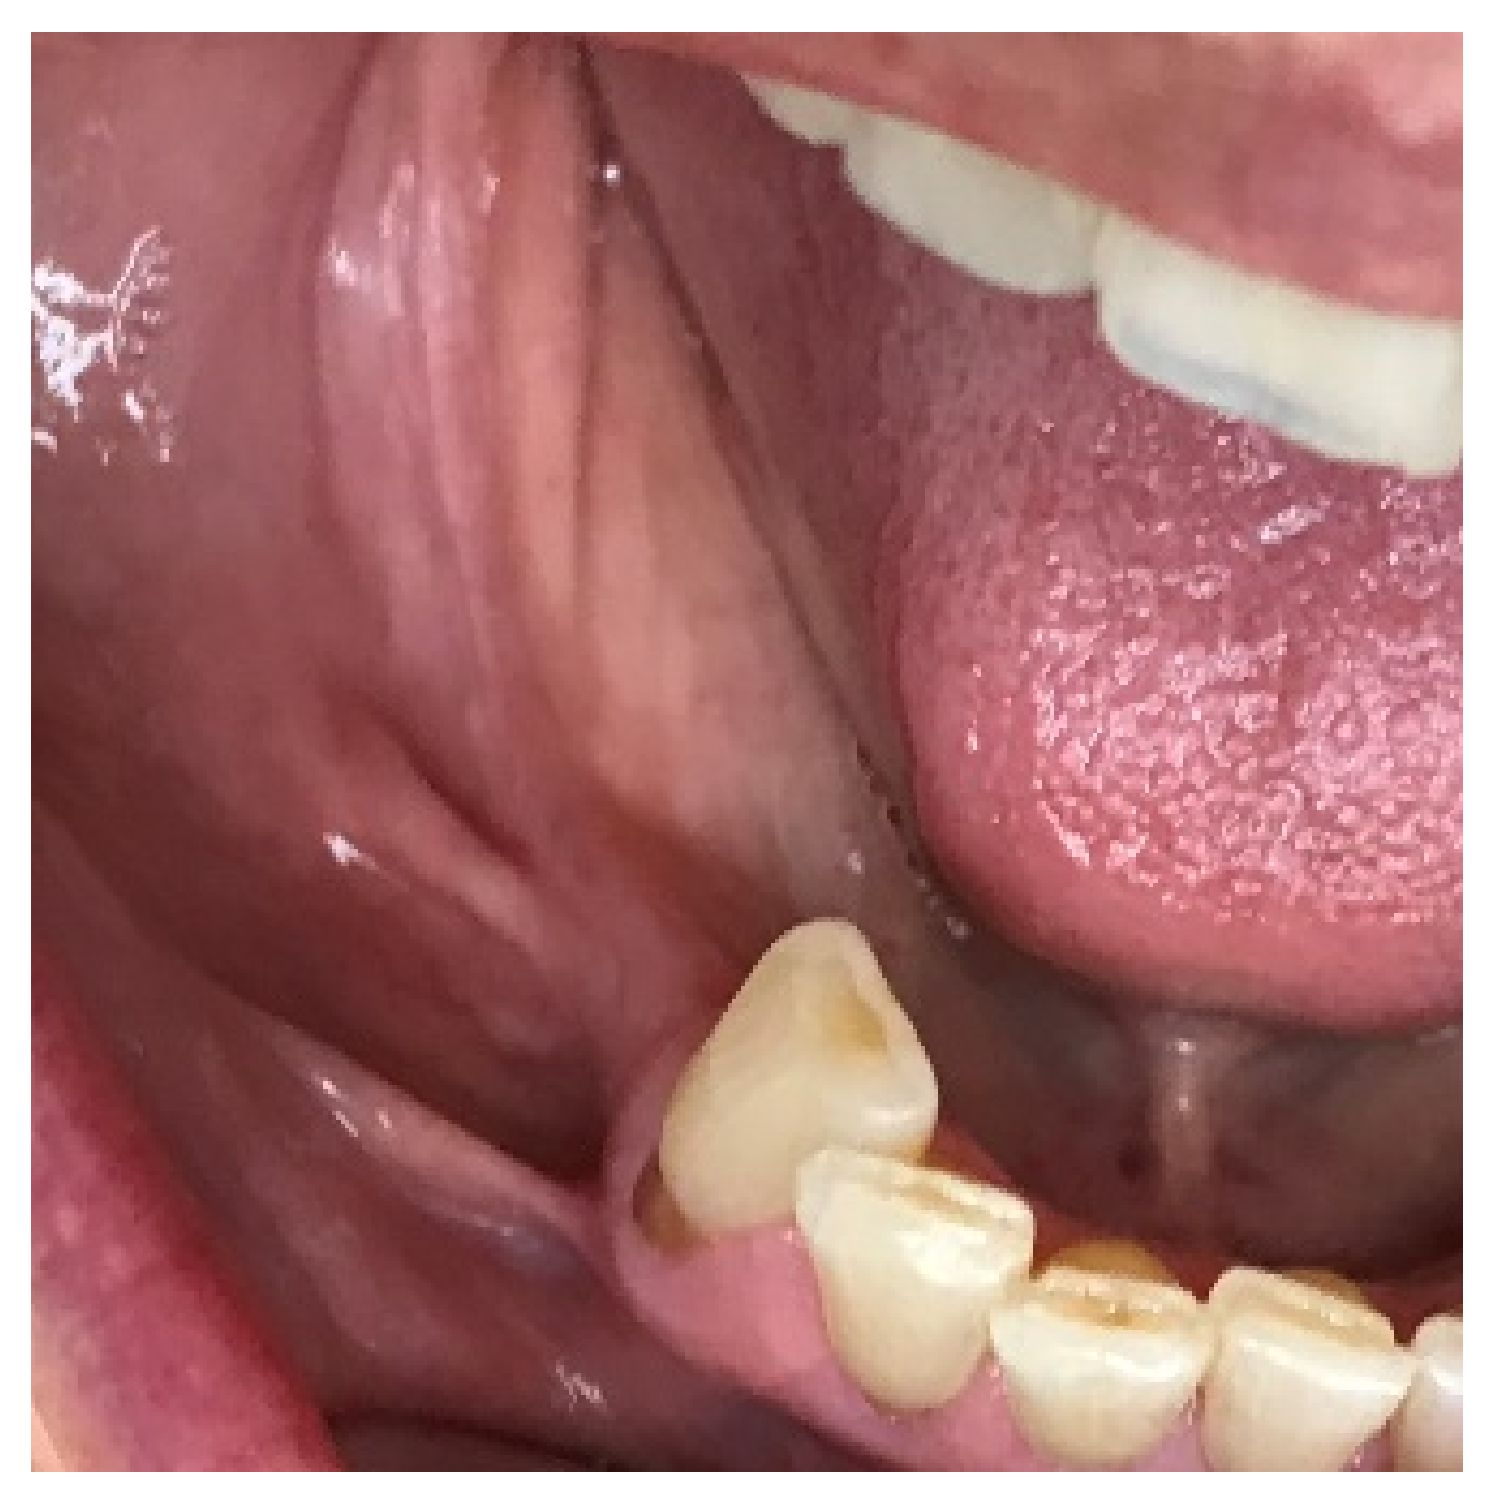

After 6 months of healing, a full-thickness flap was performed, and the screws to retain the ACBB were removed (Figure 14a,b). Three implants were placed with platform switching (Biomet 3i, T3 implants), according to the implant planning, using a surgical (prosthetic) guide. The implants were placed 1mm subcrestally, and a Puros Dermis® Allograft soft tissue matrix (Zimmer Biomet Dental) was placed over the implants to improve the thin tissue phenotype (Figure 15a,b and Figure 16).

Figure 14.

Clinical view before implant placement (a) and a full-thickness flap showing fixation (b).